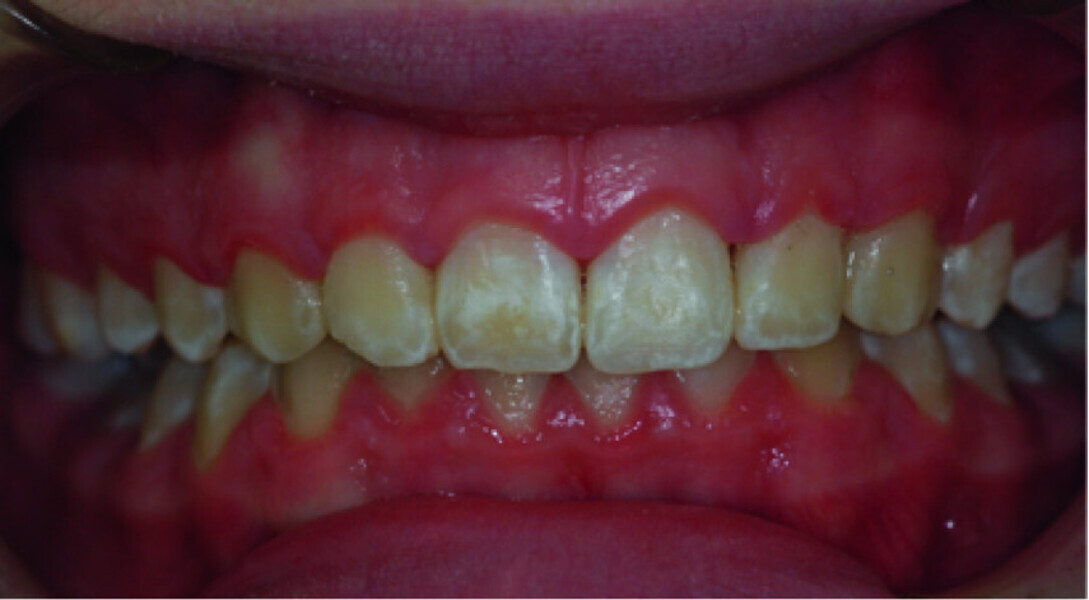

Use of diode laser in the treatment of gingival enlargement during orthodontic treatment